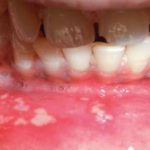

Stomatitis in children shows depending on the cause and type of disease. The main signs of stomatitis (picture 1) are: capriciousness, inflammation of the mucous membrane, cough, runny nose, fever, redness and swelling of the gums, rashes and redness in the mouth.

The most common signs of stomatitis (image 2) in children are the following:

- lethargy, capriciousness of the child, sleep disturbance, whining, nervousness, refusal to eat;

- temperature rise possible;

- pain in the mouth;

- swelling and bleeding of the gums, ulcers on the tongue and mucous membrane.